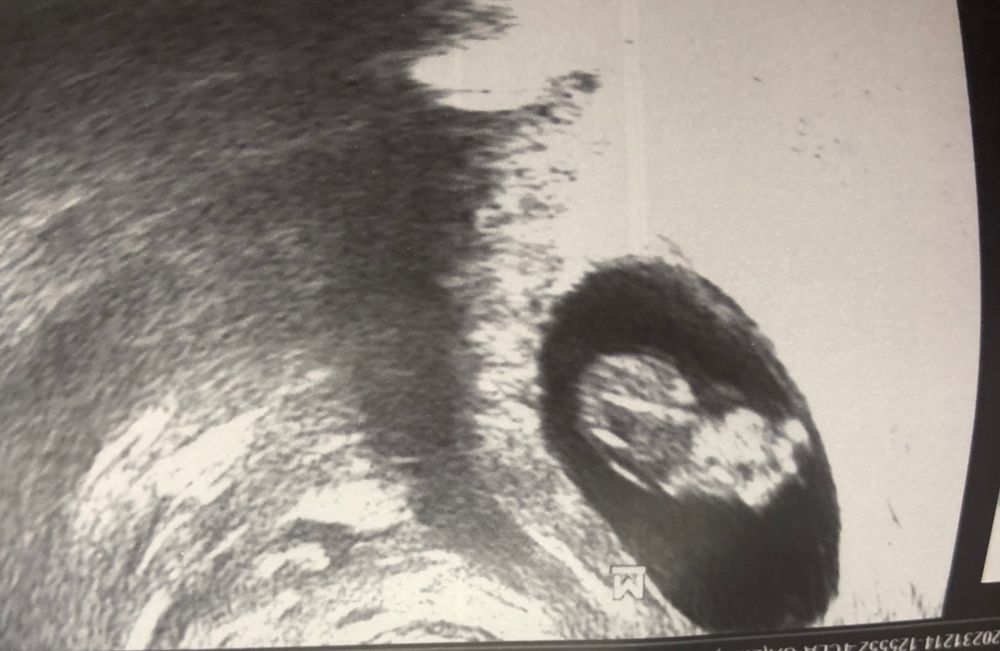

Посещение гинеколога, отслойка плодного яйца

Сегодня была у гинеколога , обнаружили причину кровянистых выделений , отслойка 19*5, около зева. Утром чуть бежево -розовое, позавчера вышел коричневый грязный цвет. Тонуса нет, малыш развивается , 8н6д КТР 2 мм, СБ 180 уд. Доктор оставил дома , постельный режим, терапия у меня домашняя :утрик, транексан, дюфастон, витамины и лежачее положение. Через неделю к нему на прием. Сказал не страшно около зева, все выходит и не пугаться😌